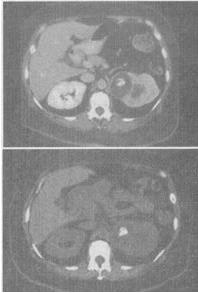

女,42岁,左侧腰痛伴尿频、尿急、尿痛,尿白细胞(++),尿细菌培养为大肠杆菌,根据所示图像,最可能的诊断是()。

A、左侧肾癌

B、左侧肾结核

C、左侧肾脓肿

D、左侧肾转移癌

E、左侧局限型黄色肉芽肿性肾盂肾炎

E